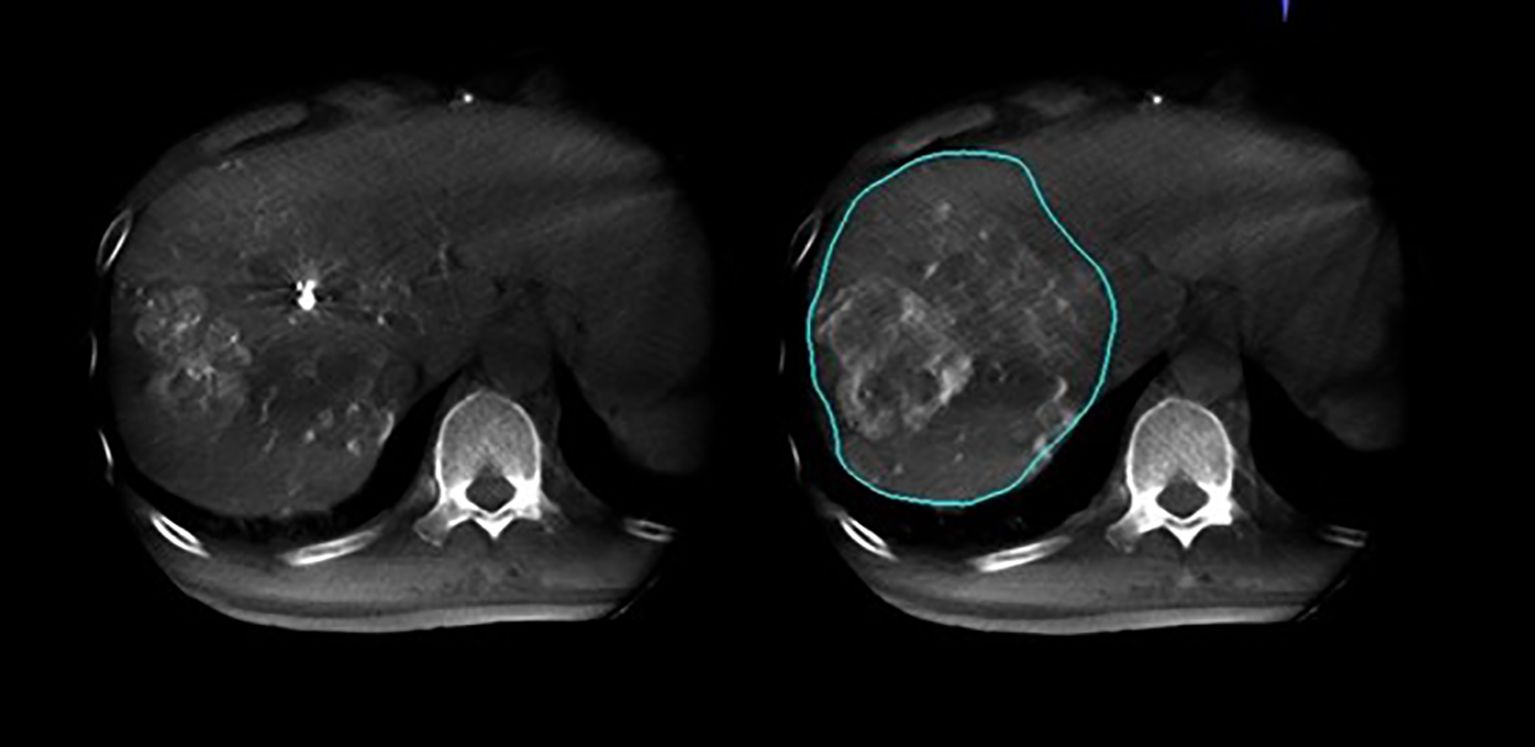

3.3 Enhanced tumor feeder arteries identification with dual CBCT

As illustrated in Figure 4 and Figure 5, conventional 2D angiography often present overlapping normal hepatic arterial branches and tumor-feeding arteries, making their distinction challenging. In contrast, dual CBCT enabled rapid and accurate identification of tumor-feeding arteries, enhancing the precision of 90Y therapy delivery. This technology successfully identified tumor-feeding arteries in all 27 cases, achieving a 100% success rate.

3.4 Optimizing tumor-feeding artery identification and catheter insertion

This study utilized dual CBCT technology to precisely locate tumors and their feeding vessels. Figure 6 and Figure 7 showed dual CBCT from the same cross-section obtained after super-selection, used to construct a 3D reconstruction model of the tumor and its blood supply vessels. The 3D model, viewed from a left anterior oblique position, clearly displays the spatial relationships between the tumor and its vessels. This detailed reconstruction significantly enhanced the precision and effectiveness of subsequent interventional procedures. Figure 8 illustrated the confirmation process conducted via arteriography after super-selection, verifying vascular localization and providing reliable data for subsequent operations.

Figure 6

CT scan of the liver featuring two panels. The left panel shows an unmarked liver image, while the right panel highlights a liver lesion with a blue outline, indicating an abnormality.

Figure 6. Dual CBCT images from the same cross-section were used to create a three-dimensional reconstruction model of the tumor.